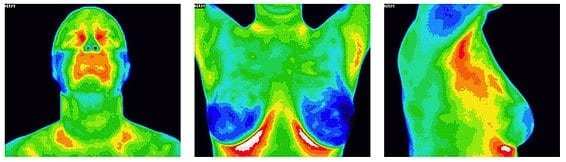

Thermography uses infrared cameras to monitor heat distribution in your body, providing a clear picture of inflammation and the early detection of disease and pathology, including suspicious breast pathology. This holistic and comfortable approach to medical screening is exceptionally accurate, and allows doctors to identify illnesses, potential illnesses, and areas of concern.

The beauty of thermography lies in its flexibility. You can use it to screen certain regions of your body such as your head or your abdomen, or you can use it to screen every single inch of your body.

In the case of whole body screening, you can get a complete look of your head, chest (breast), abdomen, arms, hands, thighs, shins, and feet.

A whole body scan can detect pain in your legs, cold spots on your body, circulatory issues, inflammation and more. This is a great “predictive indicator” for anything going on in your body, or anything that could possibly starting. Once you discover what is happening inside your body, a specialist can then treat these problems.